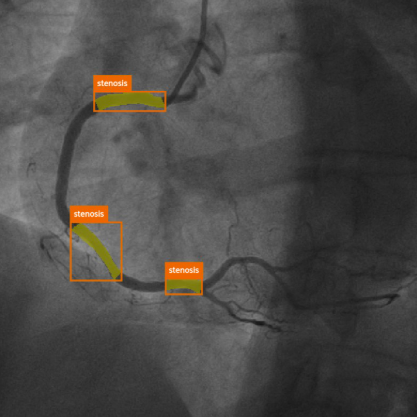

Developed a frame recommendation module based on image quality assessment (integrated into the MPXA product), local refinement module for coronary lesion & bifurcation, video-based complication detection; led MICCAI ARCADE Challenge; automated CFD (PyFluent).

Diffusion-Based User-Guided Data Augmentation for Coronary Stenosis Detection Seo S, Lee IK, Kim H-W, Min J, Jung C-H β MICCAI, 2025

SASS: Semi-Supervised Approach for Stenosis Segmentation (ARCADE Challenge) Lee IK, Shin J, Lee Y-H, Ku JH, Kim H-W β MICCAI Workshop: ARCADE, 2023